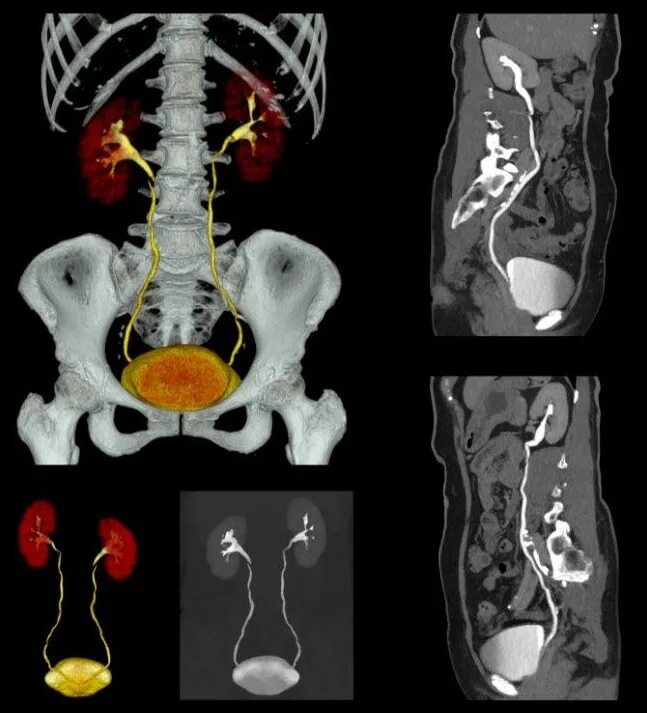

Побочный эффект кт